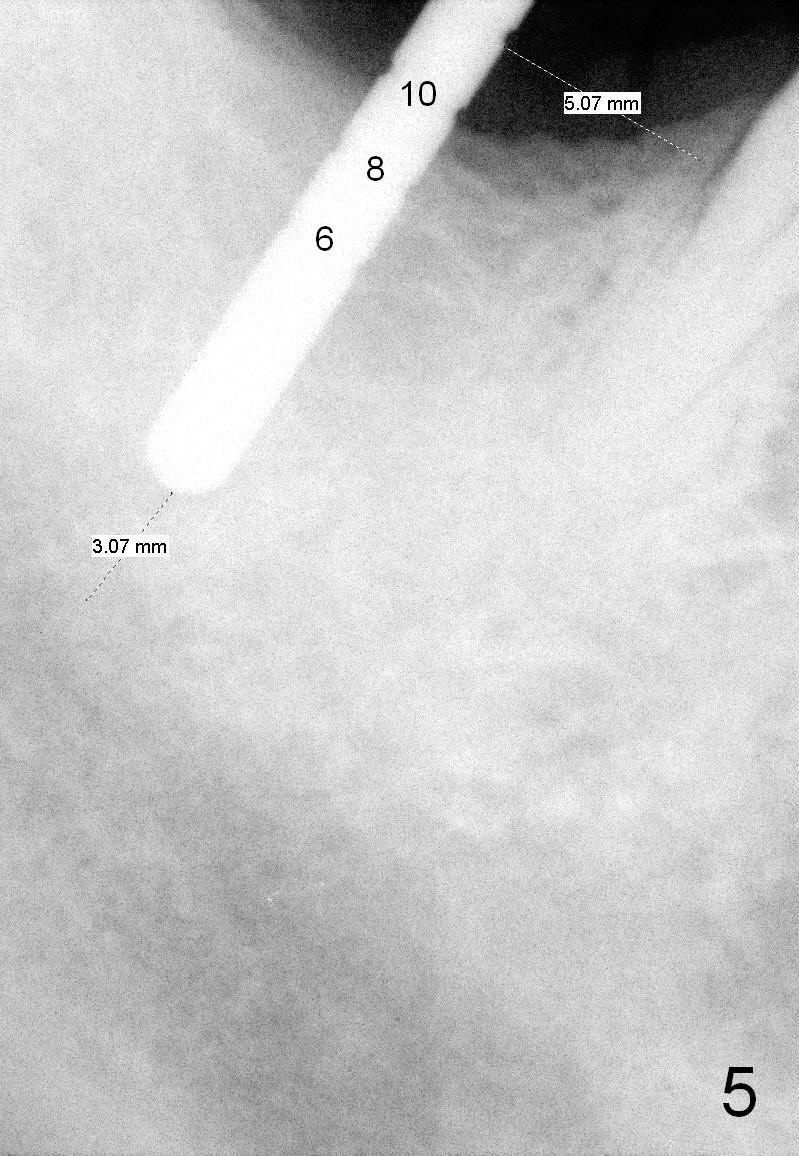

After successful immediate implant at the site of #2, he agrees to have an implant at the site of #31. The bone height has reduced to 13 mm; it appears that a 10 mm bone-level implant is appropriate (Fig.4).

When a parallel pin is inserted with the depth of 10 mm, there is 3 mm from the superior border of the Inferior Alveolar Canal (Fig.5).